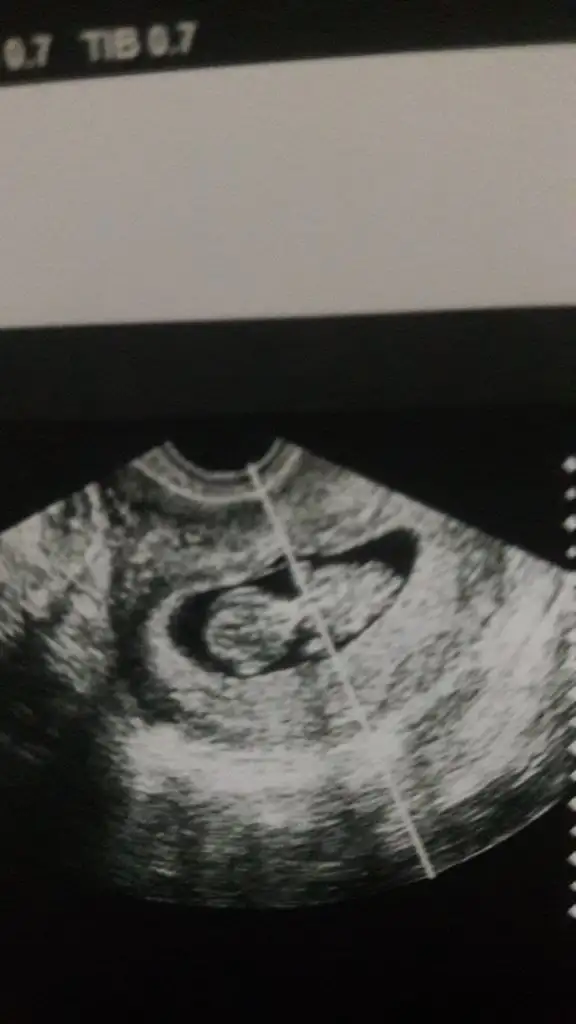

Erkeğe yatkın gibi 12_13 hafta USG de paylaşınMerhaba canım rica etsem tahmin yürütebilirmisin gerçi küçük 10+5günlük burda

Karından bakıldı ise kız sanki 11 12 13 haftalar olmalıBenim de bugün 7+3 tahmin alabilir miyim

Kaç haftalık 11 12 13 haftalar olmalıBenim bebisime de bakar misiniz cok merak ediyorum.